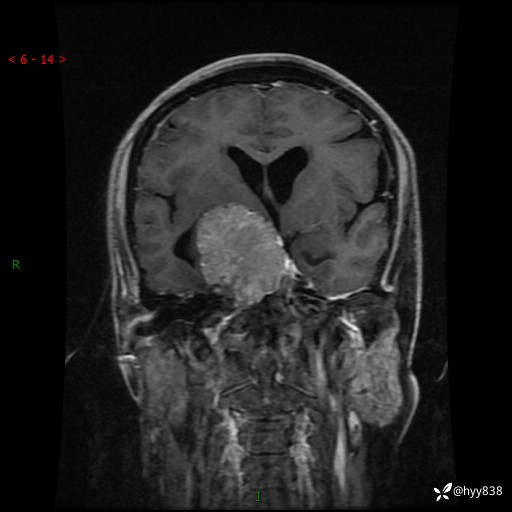

颅脑MRI平扫+增强